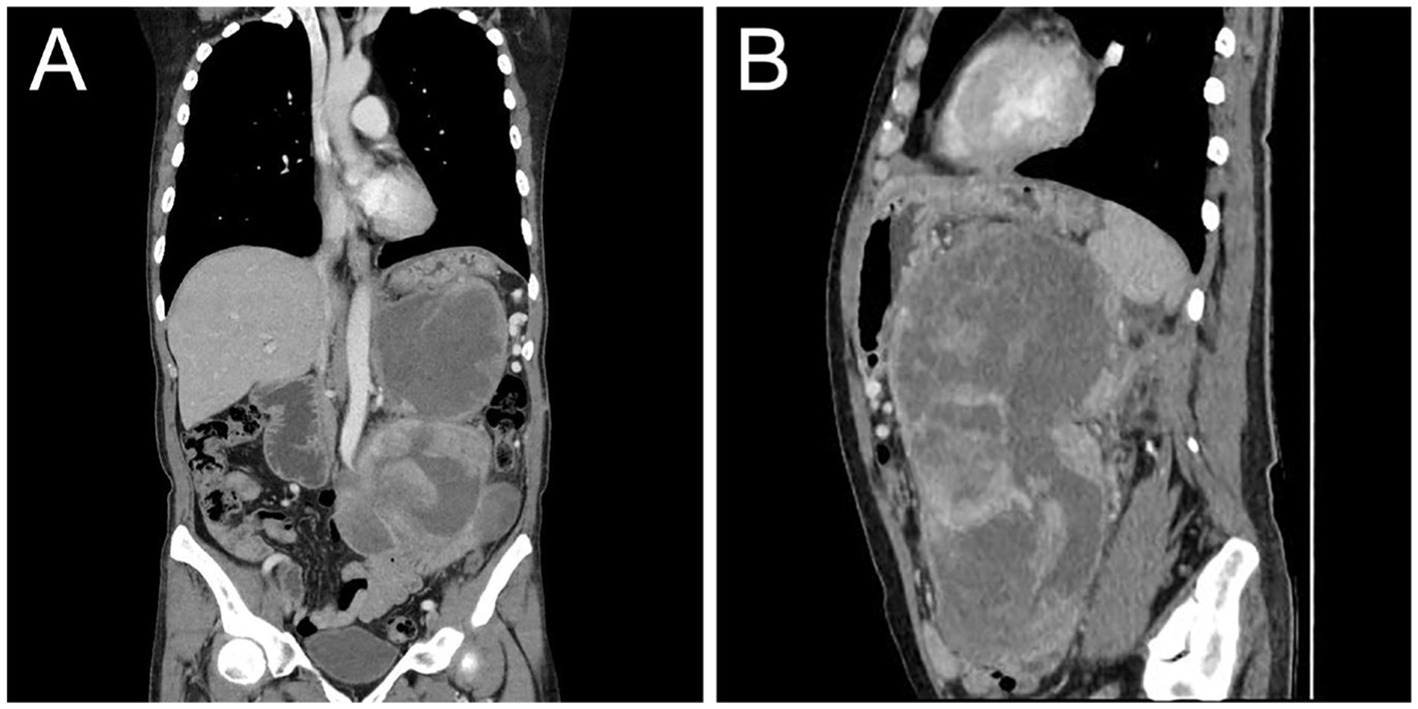

On the 10th day after surgery, the patient presented with symptoms of abdominal distension and vomiting. Physical examination revealed a palpable solid mass in the left upper abdomen, measuring approximately 20 cm × 15 cm, with limited mobility and tenderness upon pressure. Subsequent CT examination confirmed tumor recurrence (Figure 4). Despite the lack of the intended chemotherapy regimen, the patient underwent another surgical resection, revealing a retroperitoneal mass measuring approximately 20 cm × 15 cm. The mass invaded the pancreas, transverse colonic mesentery, duodenum, and spleen. Unfortunately, at the conclusion of the operation, the patient experienced a sudden cardiac arrest and could not be revived despite aggressive resuscitation efforts. The cardiac arrest was considered to be associated with the patient’s previous history of cardiac disease.

Figure 4

Postoperative contrast-enhanced CT images showed recurrence of MLS. Coronal (A) and sagittal (B) images obtained from the venous phase showed moderate inhomogeneous enhancement of the recurrent tumor in the abdominal cavity with compression and displacement of adjacent organs.